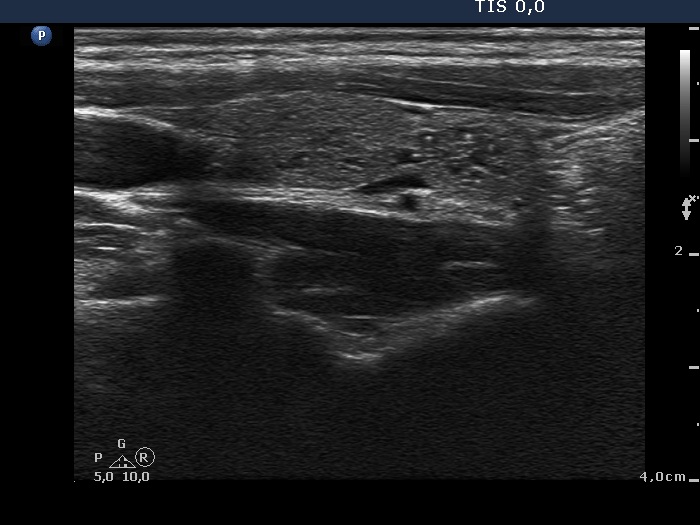

Clinical data: A 16-year-old girl was referred for evaluation of a thyroid nodule discovered on evaluation of an upper airway infection. Her complaints began three months ago and lasted for 2 weeks. Five days before present investigation she ran a temperature. A bacterial infection was diagnosed with elevated CRP levels. Antibiotics was started two days before our investigation. The fever has stopped.

Palpation: There was a tender mass in the right submandibular area. There was no abnormality in the thyroid.

Ultrasonography: The thyroid was echonormal. There was a moderately hypoechogenic inhomogeneous nodule in the lower pole of the right lobe. There were two lymph nodes next to each other above the right thyroid in the submandibular area. The lymph nodes presented a regular hilum.

Follow-up investigation one year later. The size of the thyroid nodule remained unchanged while the lymph nodes have disappeared.